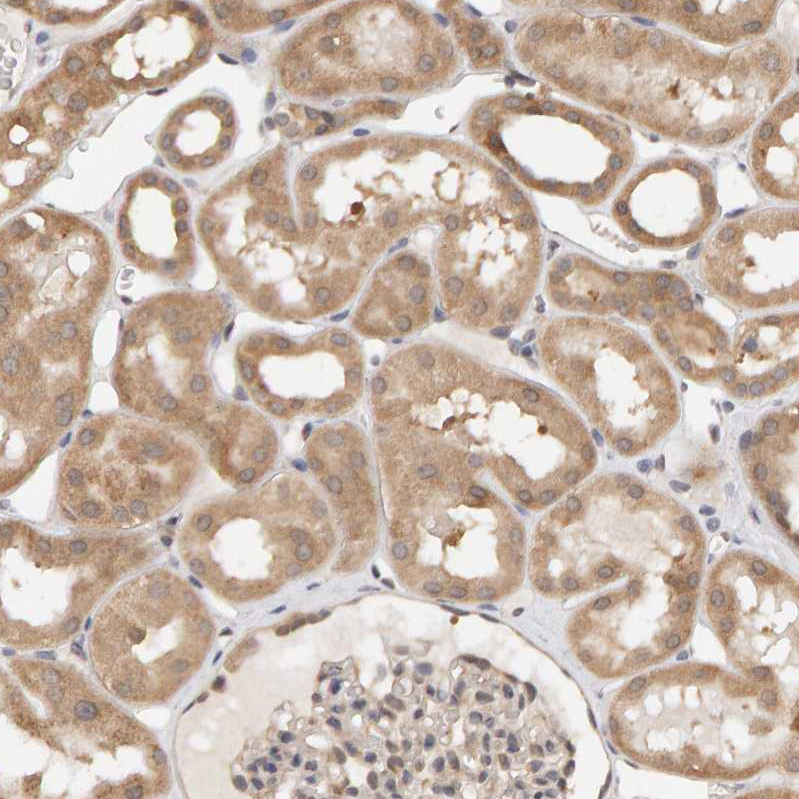

Immunohistochemical staining of human kidney shows moderate cytoplasmic positivity in cells in tubules.